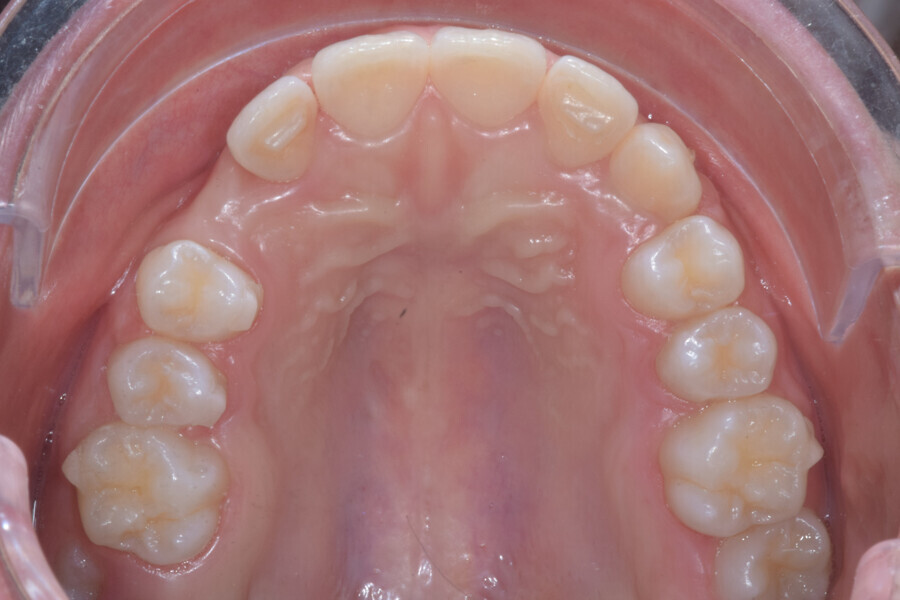

At the same time, the impacted canine was exposed by laser, a button was bonded on to it and the cantilever was connected to the button using an elastomeric thread. The final aligner was used for space maintenance while the cantilever was reactivated until the canine had erupted (Figs. 25–27). After complete eruption, further MTAs were bonded on the canine and on the lateral incisor, and a 0.014 in. NiTi archwire was used to finalise the eruption (Figs. 28–30). Only at the end of the forced eruption phase did the further aligner stage take place, aimed at achieving an ideal Class I relationship on the right by maxillary right mesialisation using Class III elastics and 27 maxillary aligners and 13 mandibular aligners (Figs. 31–33).

The overall treatment time was 16 months, 11 months of aligner treatment (five months initially for space creation and six months for finalisation after canine eruption) and five months of treatment with MTAs and sectional archwire. At the end of the treatment, a full Class I canine and molar relationship had been obtained, and the impacted canine had fully erupted (Figs. 34–38). A balanced smile with centered midlines had been achieved with an acceptable relationship between the maxillary incisors and lower lip, and torque control of the lateral and posterior segments had generated a broader smile. The limited movement of the upper lip on smiling detected at the beginning was stable, but the smile had improved in terms of expansion and the buccal corridor (Figs. 39–42).